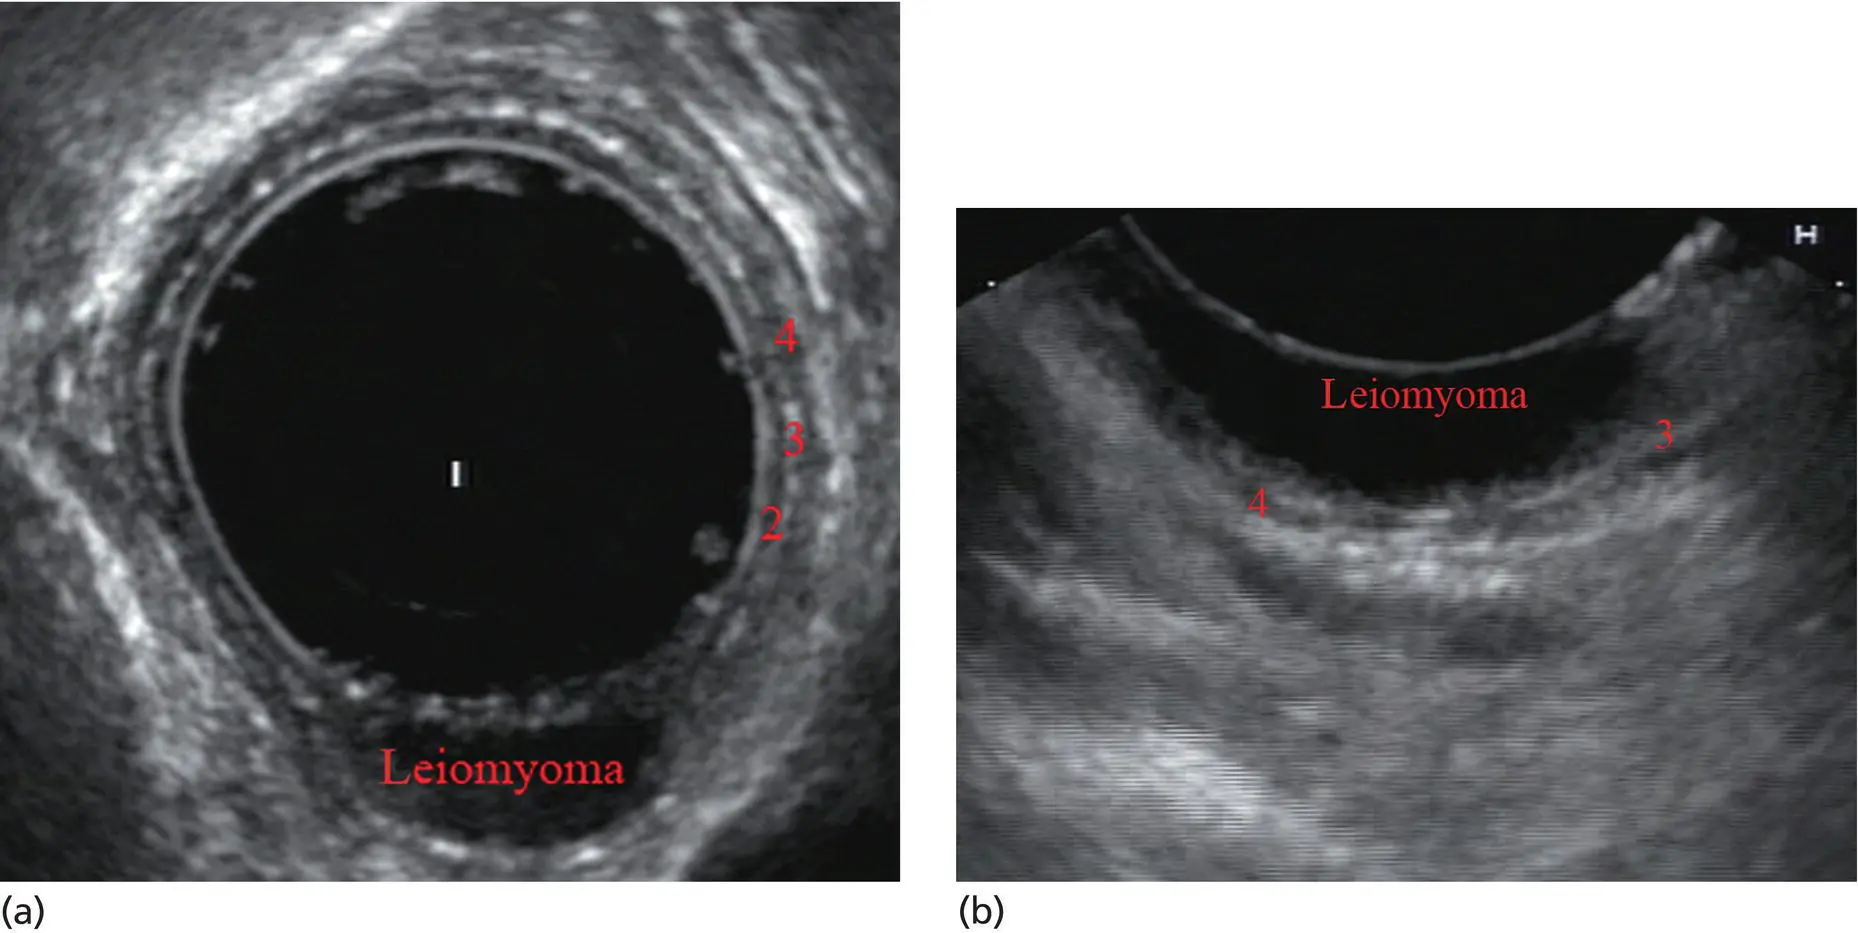

Standard examination of the esophagus and mediastinum begins with advancing the radial instrument to the gastroesophageal (GE) junction at or near the squamocolumnar junction. At this level the aorta is seen as an anechoic circular structure in the 5 o’clock position. The descending aorta is kept in this position as all radial mediastinal imaging will then correlate quite nicely with cross‐sectional imaging. Other structures visible at the level of the GE junction are the inferior vena cava (IVC) seen between 7 and 9 o’clock and the liver between 6 o’clock and 12 o’clock surrounding the IVC ( Figure 2.2).

Figure 2.2 Radial array image at gastroesophageal (GE) junction. IVC, inferior vena cava.